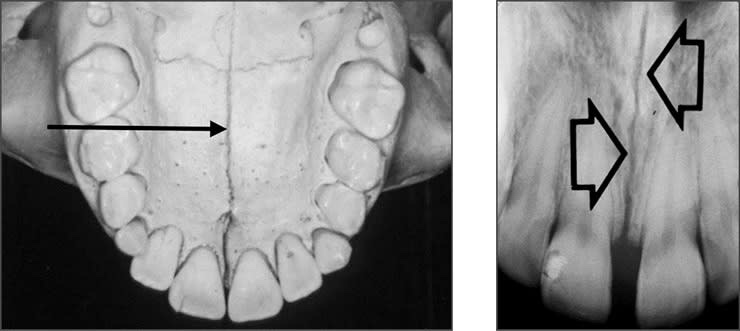

• Genial tubercle/Mental Spine– This structure serves as the locus of attachment for the genioglossus and geniohyoid muscles. It appears as spiny protuberance or prominence of bone (Doughnut-shaped) located in the midline on the lingual aspect of the mandible below the roots of the incisor teeth(2-4mm)

• Lingual foramen – Small openings located on lingual surface of mandible situated in midline & surrounded by genial tubercle.

• Mental fossa – Depression on labial surface. It has a diffuse radiolucent appearance above the mental ridge.

• Mental ridge/Triangle – Linear prominence of cortical bone located on central portion of anterior region of mandible. Occasionally seen as two bilateral inverted V-shaped radiopaque lines. Forward & upward to midline.